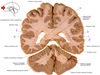

37

a

body of fornix

38

b

Septum pellucidum

39

c

Body of corpus callosum

40

d

Body of lateral ventricle

41

e

Body of caudate nucleus

42

f

Posterior limb of internal capsule

43

g

Putamen

44

h

Tail of caudate nucleus

45

i

Interpeduncular fossa

46

j

interthalamic adhesion

47

k

Inferior horn of lateral ventricle

48

L

Hypothalamus

49

m

Corona radiata